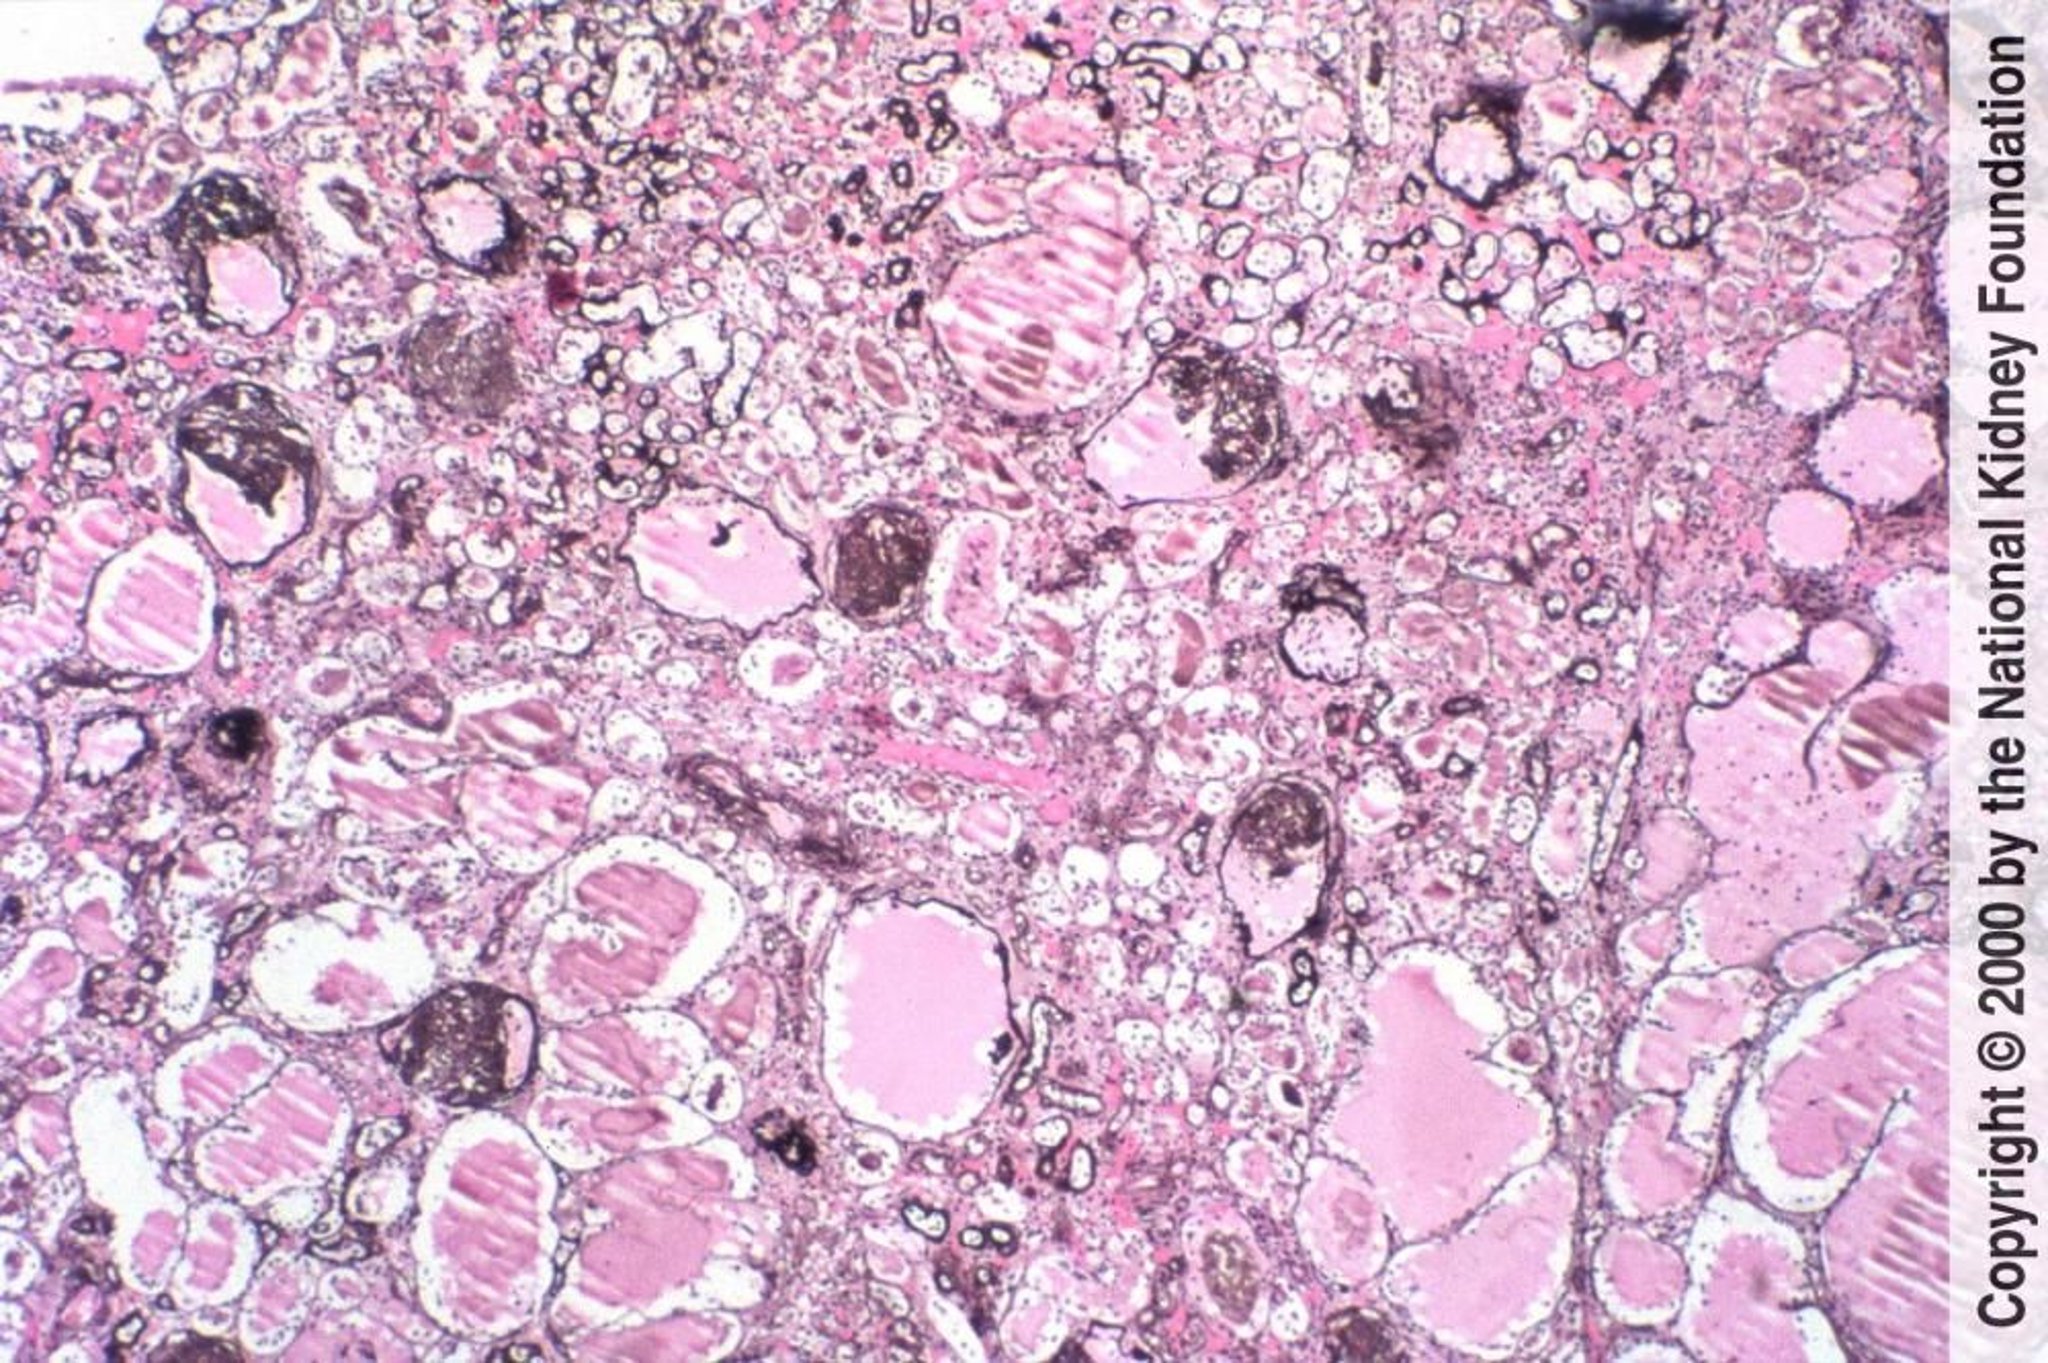

ВИЧ-ассоциированная нефропатия (коллапсирующая гломерулопатия)

Фокальный сегментарный гломерулосклероз с коллапсом почечных клубочков и микрокистозными изменениями канальцев характерен для ВИЧ-ассоциированной нефропатии (импрегнация солями серебра по Джонсу, ×100).

Image provided by Agnes Fogo, MD, and the American Journal of Kidney Diseases' Atlas of Renal Pathology (see www.ajkd.org).